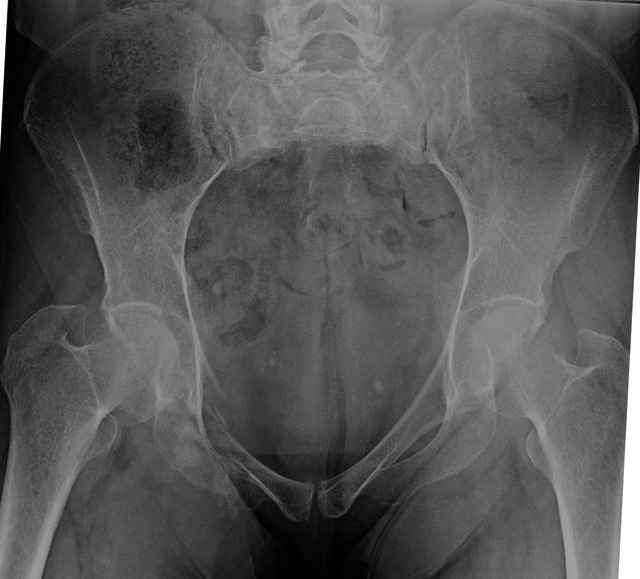

Pelvic CT Scan - 3 Months After Fall

Sacral Injuries

Ramus Fractures